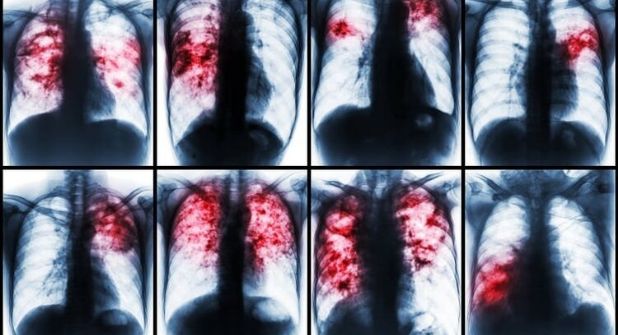

La región fronteriza con México hace latente la posible aparición de casos en Laredo y su área. La tuberculosis es una enfermedad bacteriana infecciosa, potencialmente grave, que afecta principalmente a los pulmones.

La bacteria que ocasiona la tuberculosis se propaga cuando una persona infectada tose o estornuda. La mayoría de las personas infectadas con la bacteria que causa la tuberculosis no tienen síntomas.